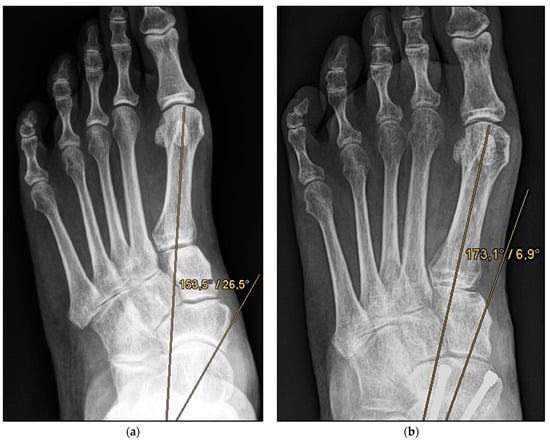

Figure 2.

Pre- and post-operative radiographic findings of combined talonavicular arthrodesis and calcaneal displacement osteotomy, left foot. (a) Anteroposterior view pre-operative, (b) anteroposterior view post-operative.

Figure 4.

Pre- and post-operative radiographic findings of double arthrodesis, left foot. (a) Anteroposterior view pre-operative, (b) anteroposterior view post-operative.